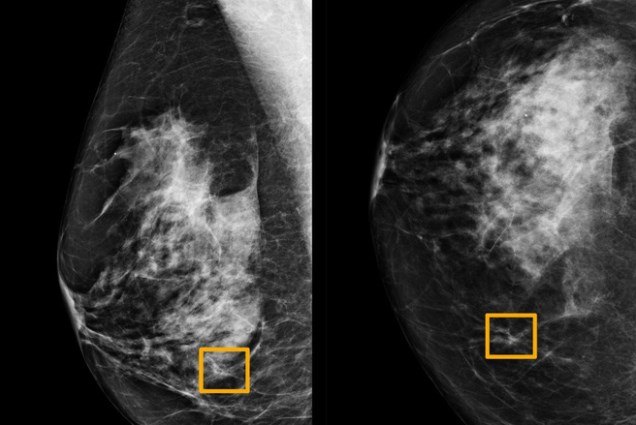

Ô vàng là nơi trí tuệ nhân tạo tìm thấy ung thư ẩn bên trong mô vú. Ảnh: Đại học Northwestern.

Đồng thời, kết quả âm tính giả - khi ung thứ vú không bị phát hiện, cũng giảm 9,4% với các bệnh nhân tại Mỹ, và 2,7% với các bệnh nhân người Anh.